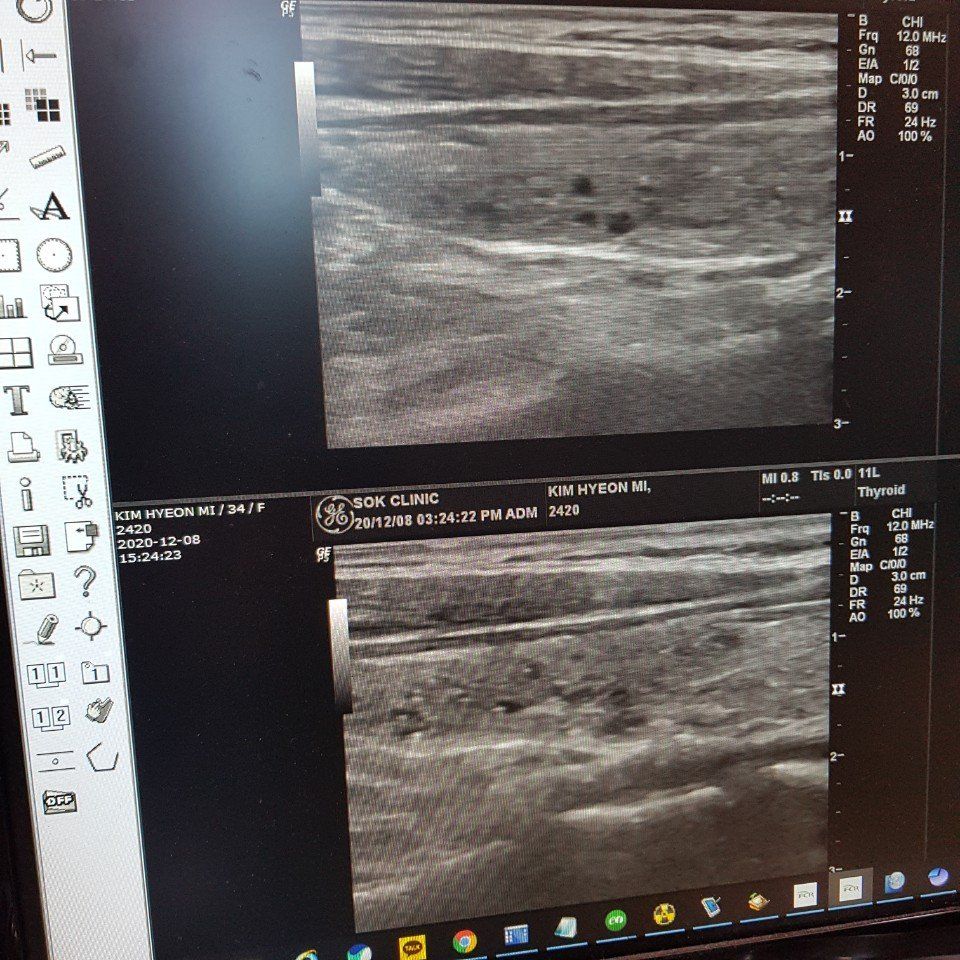

갑상선초음파 검사결과 혹이 발견되었습니다. 암인가요?

와이프가 체중도 급격히 빠지고 해서 병원에서 갑상선 초음파 검사를 했습니다.

갑상선에 0.1mm 혹이 대략 10개정도 있다고 하더라구요.

초음파 사진 첨부하오니 판독 부탁드립니다.

• 1번 째 사진